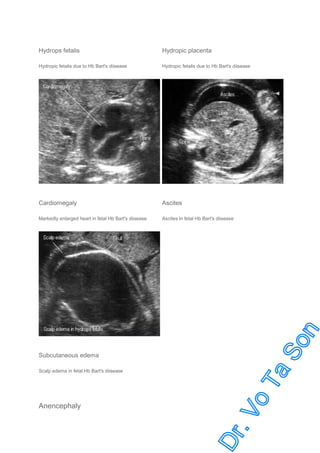

Sonographic Findings of Hb Bart’s disease

•

cardiomegaly (increased cardio-thoracic ratio from midpregnancy) (The earliest sign)

Placentomegaly

Ascites

Pleural or pericardial effusion

Subcutaneous edema (late sign)

Oligohydramnios (in late pregnancy) (unlike other causes which commonly related to polyhydramnios)

Hydrops fetalis

Hydropic placenta

Hydropic fetalis due to Hb Bart's diisease

Cardiomegaly

Markedly enlarged heart in fetal Hb Bart's diisease

Ascites in fetal Hb Bart's diisease

Subcutaneous edema

Scalp edema in fetal Hb Bart's diisease